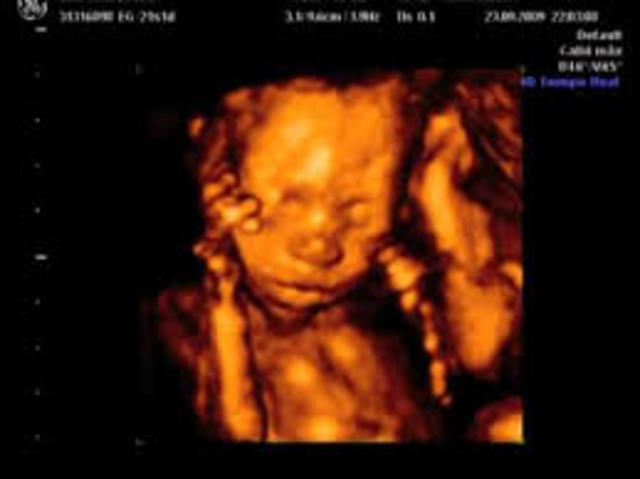

Algunos estudios señalan que en esta etapa de desarrollo el bebé mueve en exceso los ojos, lo que indicaría que quizás sueña, aún sin haber nacido. En la semana 33 de embarazo el cerebro de tu bebé sigue en pleno desarrollo y debes saber que sus cinco sentid